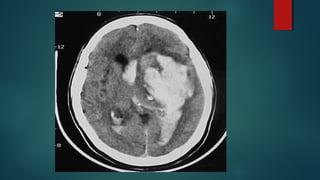

Este documento es el programa para un taller de imágenes del curso de emergencia 2015 impartido por el Dr. Víctor Delgado. El taller se centra en el uso de imágenes médicas para el diagnóstico y tratamiento de pacientes en coma traumático según la base de datos de Marshall. El Dr. Delgado es el único instructor repetido a lo largo del documento.